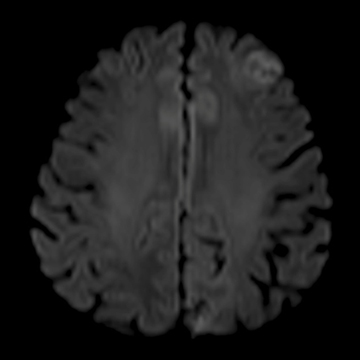

Diffusion, b-value 1000, iPAT 2

MRI画像例

左右にスクロールして画像をご覧いただけます。

頭部ルーティーン